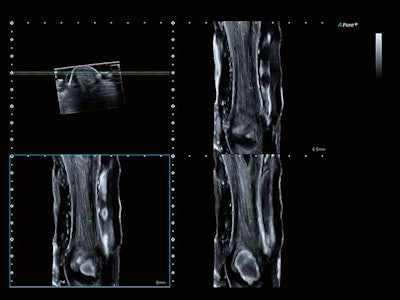

The company's Aplio i800 now features a 33-MHz linear-array transducer that is designed to offer better spatial resolution below 50 microns and improved resolution and detail for B-mode and color flow imaging. Its Smart Sensor 3D allows users to take 3D volumes with a standard linear or convex transducer. The system is particularly suitable for superficial subcutaneous imaging and examinations of small joints and superficial nerves, as well as for superficial vascular evaluations.